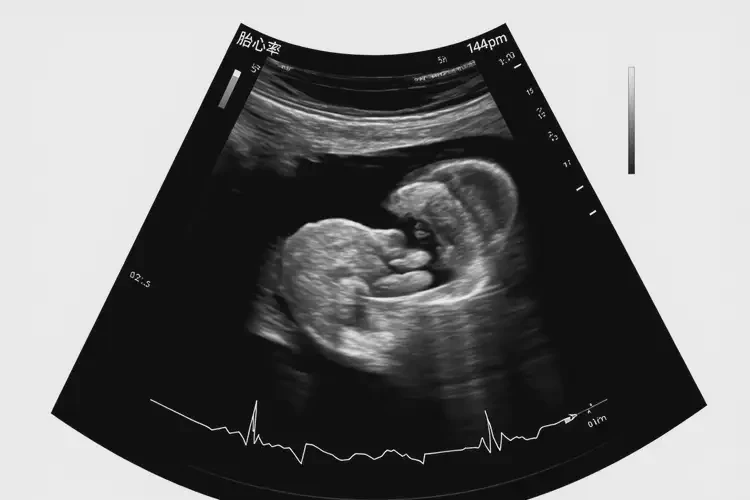

懷孕3周胎心144正常嗎

胎心率144次/分鐘在懷孕3周時是正常的。

在懷孕早期,胎心率通常在120-160次/分鐘之間波動。胎心率是指胎兒心臟每分鐘跳動的次數(shù),它反映了胎兒的健康狀況。在懷孕3周時,胎兒的心臟已經(jīng)開始跳動,但由于胎兒還很小,胎心率可能會有一定的波動。

懷孕3周胎心144正常嗎(圖1)